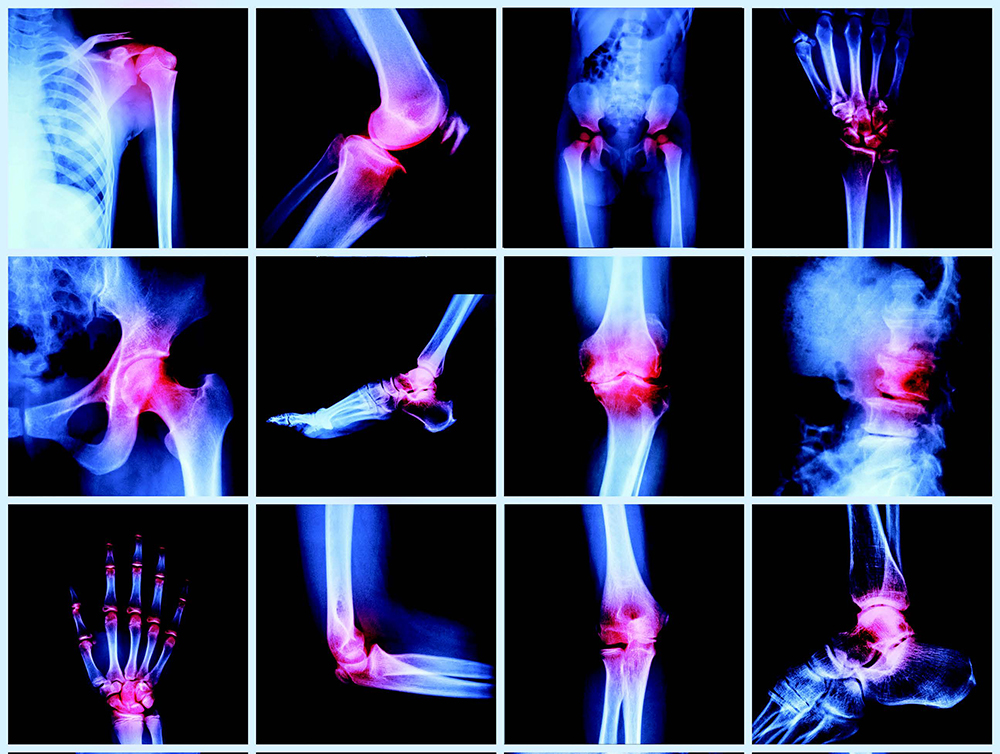

Simptomat që tregojnë se vuajmë nga artriti

Foto: Ilustrim

Artriti është një term që grupon më shumë se 100 sëmundje dhe çrregullime të ndryshme autoimunitare që shkaktojnë dhimbje, ngurtësim dhe ënjtje të kyçeve dhe nyjave. Sëmundjet autoimunitare zakonisht kanë të bëjnë me një sistem imunitar që sulmon organizmin. Një sulm i tillë kryhet nga rruazat e bardha të gjakut që në vend se të sulmojnë bakteret dhe infeksionet, godasin indet e shëndetshme rreth kyçeve.

Format më të përhapura të artriti janë: osteoartriti, reumatizma dhe fibromialgjia. Secila prej sëmundjeve në fjalë ka shenja dhe simptoma karakteristike por që në disa raste ndërthuren me njëra tjetrën. Përveç simptomave të dukshme që prekin kyçet, këto sëmundje si artriti apo reumatizma manifestohen edhe me simptoma të tjera.